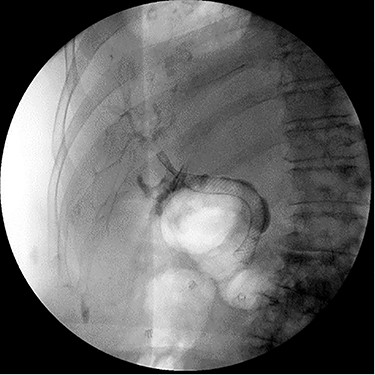

Despite external drainage, the patient experienced persistent bilious output from the JP drain. A rendezvous procedure was performed; cholangiography visualized the dilated bilateral intrahepatic ducts with narrowing at the proximal CBD. Via a simultaneous endoscopic approach, the distal CBD was successfully cannulated and balloon dilated. A 10 x 60 mm covered fluency (BARD) stent was deployed. Completion cholangiogram demonstrated contrast flowing to the duodenum with no extravasation. The patient recovered well and was subsequently discharged (Fig. 2).

ERCP demonstrating successful rendezvous with deployment of metal stent in the vicinity of surgical drain.